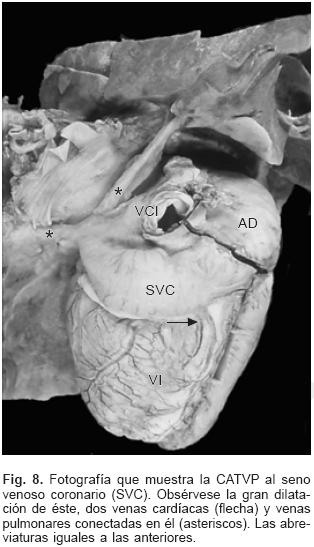

En la CATVP al atrio derecho el SVP se integra en la parte posterosuperior de esta cámara a través de un colector muy corto (Fig. 7). En el sitio de conexión al seno venoso coronario el colector venoso desembocó en el extremo izquierdo de dicho seno el cual estuvo dilatado (Figs. 2 y 8). El orificio de desembocadura del seno venoso coronario en el atrio derecho fue muy amplio y se situó por debajo de la comunicación interatrial (Fig. 9). En un espécimen existió estrechez intrínseca del colector en el sitio en que se unió al seno venoso coronario. En la conexión anómala infradiafragmática el SVP recibió las venas de ambos pulmones y se continuó con un colector largo que acompañó al esófago, atravesó el hiato esofágico y descendió hasta desembocar en la vena porta justo antes de penetrar al hígado (Fig. 10). Todos los corazones de este grupo presentaron obstrucción extrínseca a nivel del hiato esofágico y en dos especímenes se agregó obstrucción intrínseca en el colector antes de su desembocadura en la vena porta (Fig. 10).